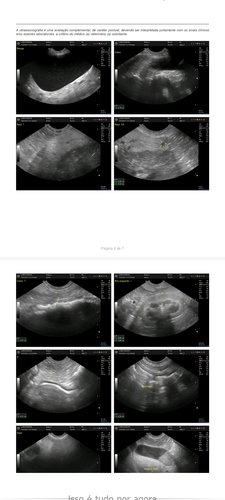

Laudos em anexo!